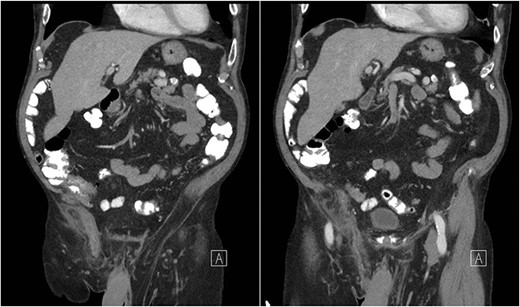

An 81-year-old male with a past medical history of childhood repair of cardiac septal defect presented to our emergency department (ED) with a two-day history of vague abdominal pain that migrated to his right groin with an associated non-reducible right groin mass. The non-reducible groin mass persisted, and his pain progressed that prompted him to come to the ED. Clinical examination revealed a firm, tender and irreducible right inguinal mass. The remaining clinical and laboratory tests were normal. Contrast-enhanced computed tomography (CT) of the abdomen and pelvis was performed. CT presented an acute appendicitis within a right inguinal hernia and a dilated appendix, measuring 13 mm in diameter and demonstrated periappendiceal fat stranding with no evidence of rupture (Figs 1–3). Patients’ history, physical exam and imaging findings were consistent with the preoperative diagnosis of an Amyand’s hernia with acute appendicitis. It was determined the patient will require operative intervention.

Coronal CT abdomen with oral contrast showing a dilated appendix periappendiceal fat stranding within a right inguinal hernia and no evidence of rupture.